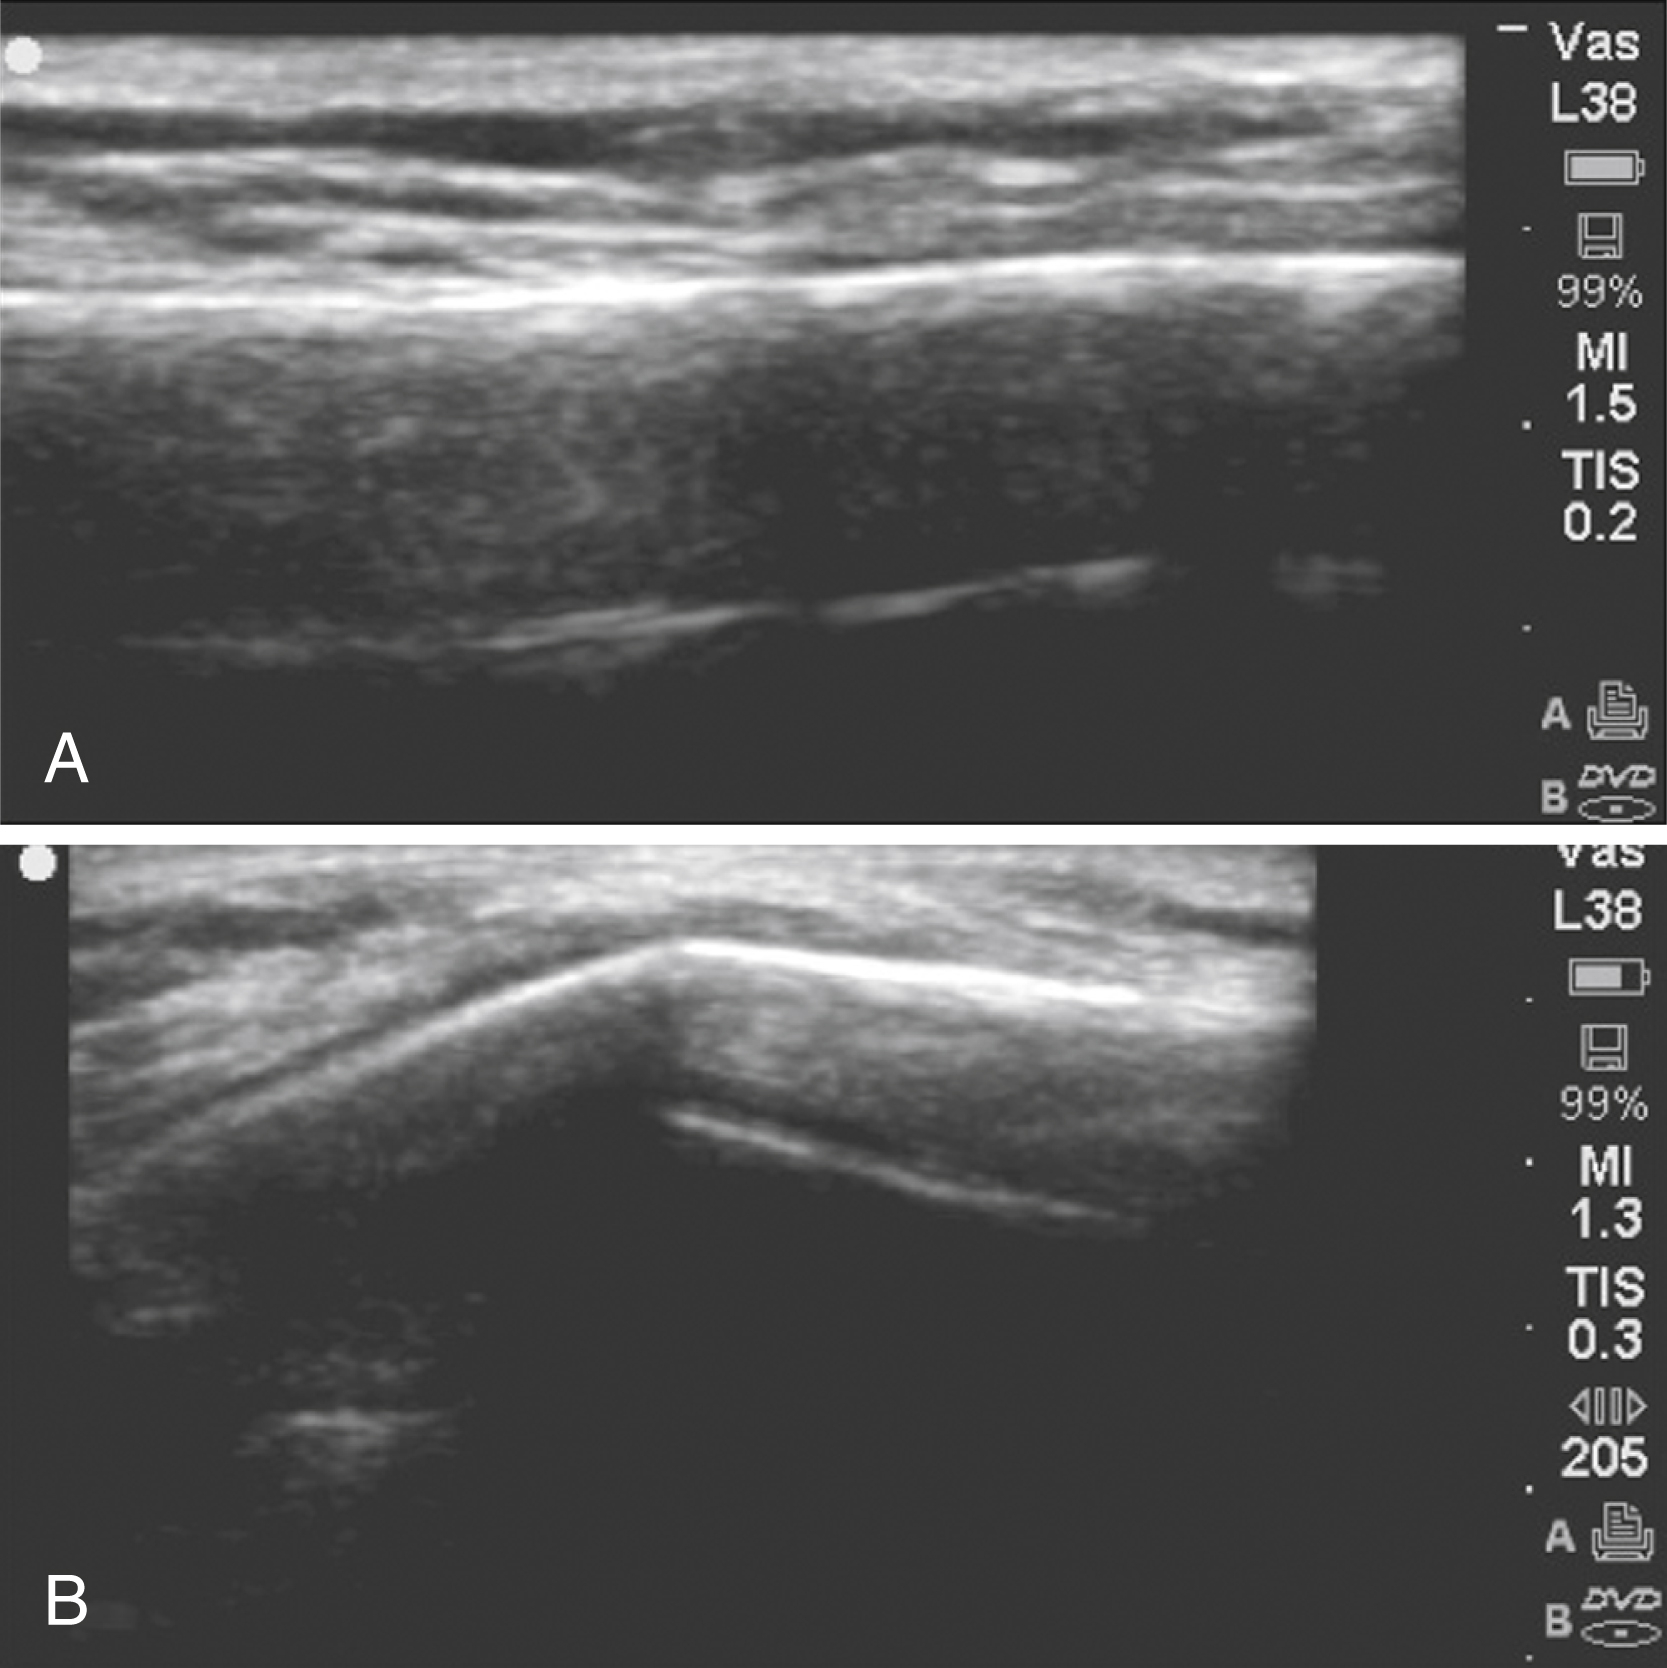

Clavicle-specific plain radiographs may be required to confirm the presence of a fracture, although most clinically significant fractures are diagnosed on chest or shoulder radiographs. Fractures in children can be reliably diagnosed or ruled out by POCUS, decreasing the exposure to radiation ( Fig. 45.8 ).

Ultrasound images of the clavicle. (A) Normal. (B) Midclavicular fracture.

Courtesy Keith Cross, MD.